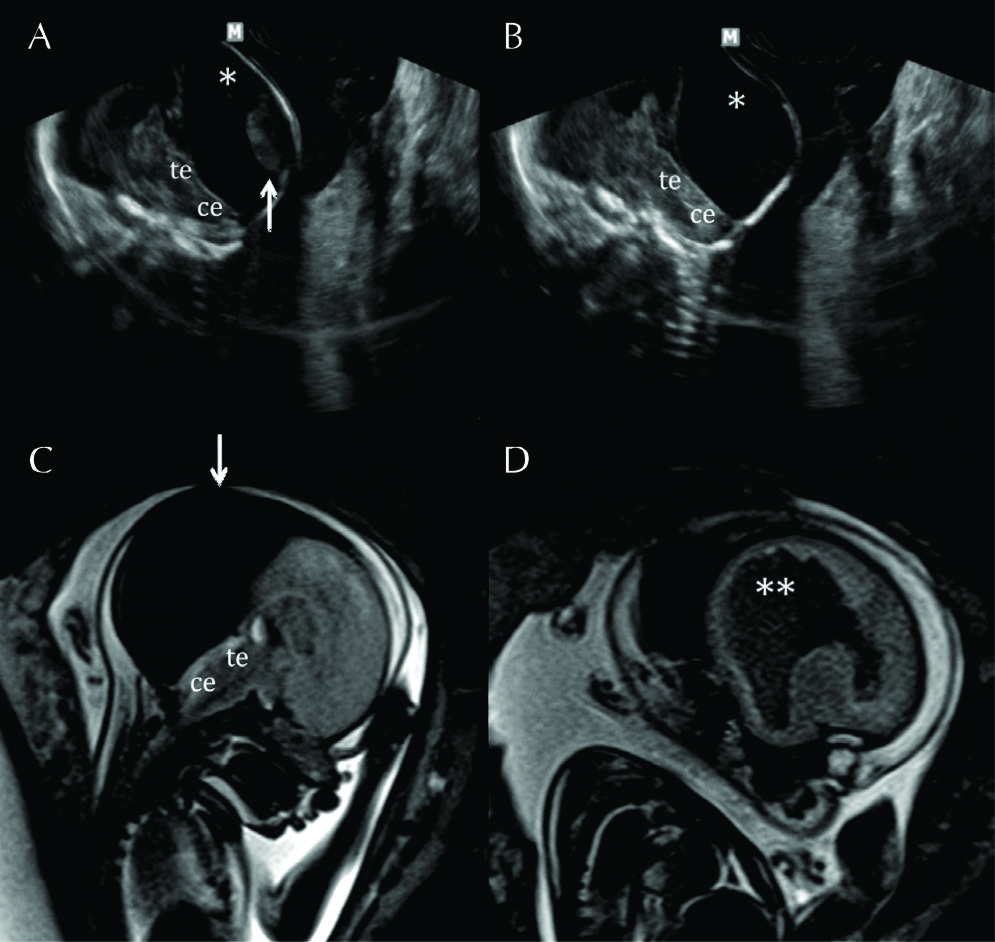

Figura 10

RM Fetal en Malformación de Chiari.

Estudio realizado a las 29 semanas con diagnóstico ecográfico de mielomeningocele. En imagen coronal (A) se observa la severa dilatación del sistema ventricular supra-tentorial lo que se corrobora en la imagen axial (B) con una disposición colpocefálica de los ventrículos laterales (VL). En la imagen fetal sagital (C) se reconocen el cerebelo (Ce) y tronco encefálico (Te) sin identificarse claramente el IV ventrículo lo que indica una disminución de las dimensiones de la fosa posterior. En el mismo plano se observa el defecto de cierre posterior del tubo neural (è) con un saco de meningocele. La imagen axial a nivel de ese saco (D) muestra claramente el defecto espinal posterior (è) aunque sin observarse claramente el contenido neural del mismo.

Figura 11

RM Fetal Esquizencefalia bilateral.

Estudio de RM realizado en la semana 29 con diagnóstico ecográfico de esquizencefalia bilateral. En el corte axial (A) y coronal (B) se reconocen las clásicas hendiduras que vinculan el sistema ventricular con el espacio sub-aracnoideo de la convexidad en ambos hemisferios.

Las estructuras de línea media son normales así como también el tronco encefálico (Te) y el resto de las estructuras intra-craneanas.